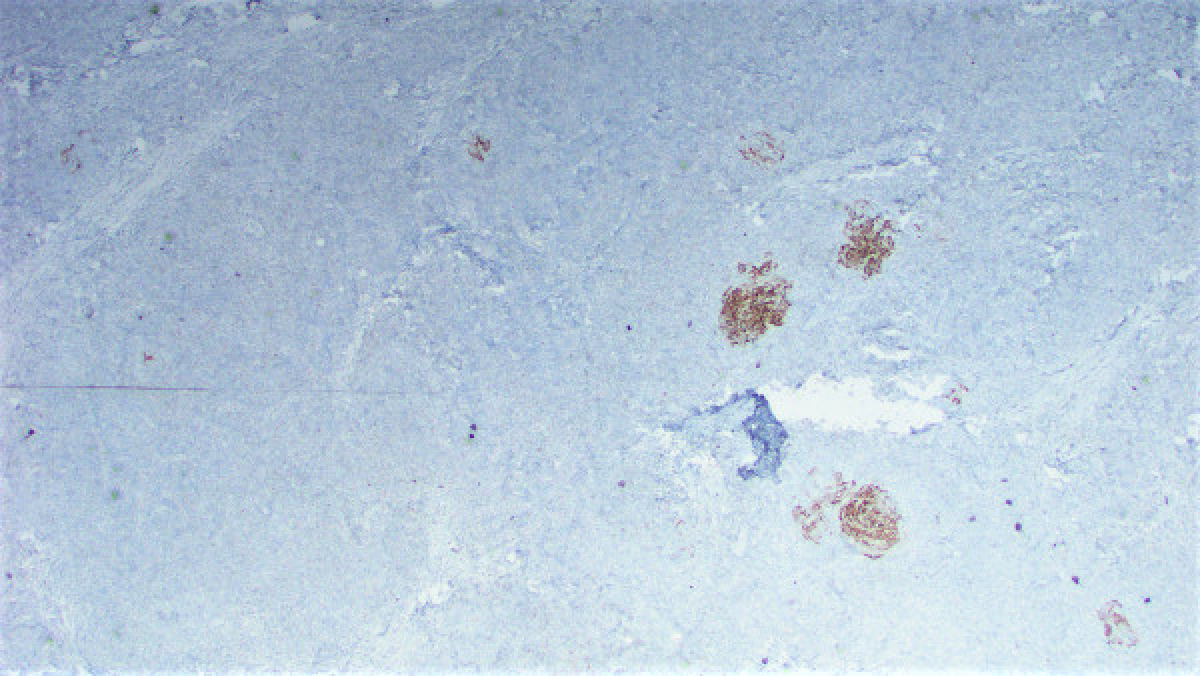

Three months ago the patient presented with a pink rash on the upper right arm. This was treated with topical steroids and the biopsy of that lesion revealed a reactive lymphoid proliferation. One month later the patient noticed a raised lesion on her upper right arm. An excisional biopsy of this lesion was performed. This biopsy revealed a vaguely nodular dermal infiltrate composed of a mixture of small cells with a high nuclear:cytoplasmic ratio and some larger cells with a plasmacytoid appearance (Figures 1 and 2). Immunohistochemical stains were performed and revealed both populations of cells to diffusely express CD20 (Figure 3) while negative for CD23 (Figure 4) and BCL-6 (Figure 5). There were scattered CD3 lymphocytes (Figure 6). Ki-67 was low (~20-30%), but elevated within residual germinal centers. Flow cytometry revealed lambda-restricted B cells, negative for CD5 and CD10.